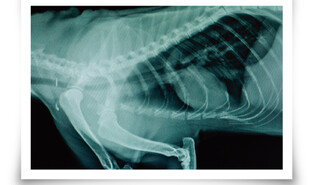

헤어볼을 토하는 경우가 많다 보니 고양이가 구토 증상을 보여도 대수롭지 않게 여길 수 있다. 하지만 일주일에 2번 이상 구토하거나, 근래 들어 구토가 잦고 식욕이 떨어졌다면 병원을 찾아야 한다. 이물질 섭취가 확인되면 상황에 따라 다양한 처치가 이뤄진다. 삼킨 지 얼마 안 된 작은 이물질이 위에 있다면 구토를 유발해 배출시키거나, 내시경으로 제거를 시도할 수 있다. 하지만 이미 장까지 이물질이 내려갔거나 뾰족한 형태라면 내시경으로 꺼내기 힘들기 때문에 수술로 없애야 한다.